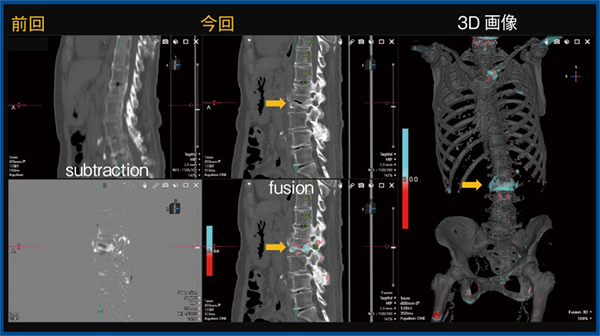

3.大腸がん術後,下肢麻痺

図3は,大腸がん術後で肺転移があり,下肢麻痺の症状で受診された症例である。TSBの3D画像では,胸椎に溶骨性変化を疑う赤い領域(図3 ←)を認め,横断像では椎弓や棘突起が破壊されているのがわかる(○)。TSBは骨の変化のみを解析しているため,病変の脊柱管進展については検出されない。本症例では,症状からも脊柱管進展が疑われたため,軟部条件で観察したところ,高度な進展を認めた(図3 b)。しかしながら,症例によっては脊柱管進展が軽微な場合もあるため,TSBの解析結果に加えて読影者自身が進展の有無を確認することが必要である。

なお,本症例は,前回のCTで椎体への転移を指摘できなかった症例である。振り返ってTSBで解析を行ったところ,同部位に溶骨性変化を指摘しており,その時点では脊柱管への進展は来していなかった。前回のCT撮影時はTSB導入前であったものの,TSBで解析を行っていたら下肢麻痺は防げた可能性がある一例である。

図3 大腸がん術後,下肢麻痺